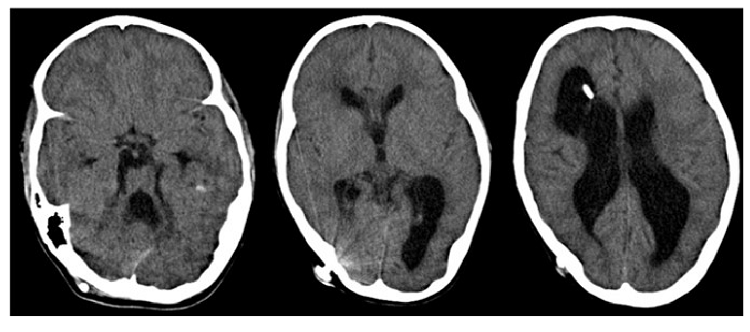

Un año después del tercer episodio, la niña acudió a consulta de neurooftalmología. En el examen se reportó gran ventriculomegalia sin edema transependimario.

En ambos ojos la agudeza visual le permitía percibir el movimiento de manos a 30 cm, pero la visión cromática era nula. El diámetro de las pupilas era de 5 mm en la luz y de 6 mm en la penumbra. El reflejo fotomotor directo era de 1 en el ojo derecho y de 2 en el izquierdo; se evidenciaba defecto pupilar aferente relativo en el ojo derecho. En el examen del fondo de ojo, los discos ópticos eran redondos, con contornos definidos, pálidos, excavación de 0,4 mm y no había cortocircuito óptico-ciliar. En el sistema visual eferente, los párpados y la motilidad ocular eran normales, y se producía nistagmo con la mirada extrema pendular.

El diagnóstico final después del tercer episodio fue de atrofia óptica bilateral, parálisis cerebral mixta espástico-distónica de predominio izquierdo, hidrocefalia con derivación ventrículo-peritoneal, discapacidad intelectual y física (con deficiencia visual en seguimiento), leucomalacia periventricular y síndrome de ventrículos rígidos. En la figura 3 se presenta una síntesis gráfica de la evolución de la paciente, con los principales momentos clínicos y los resultados obtenidos.